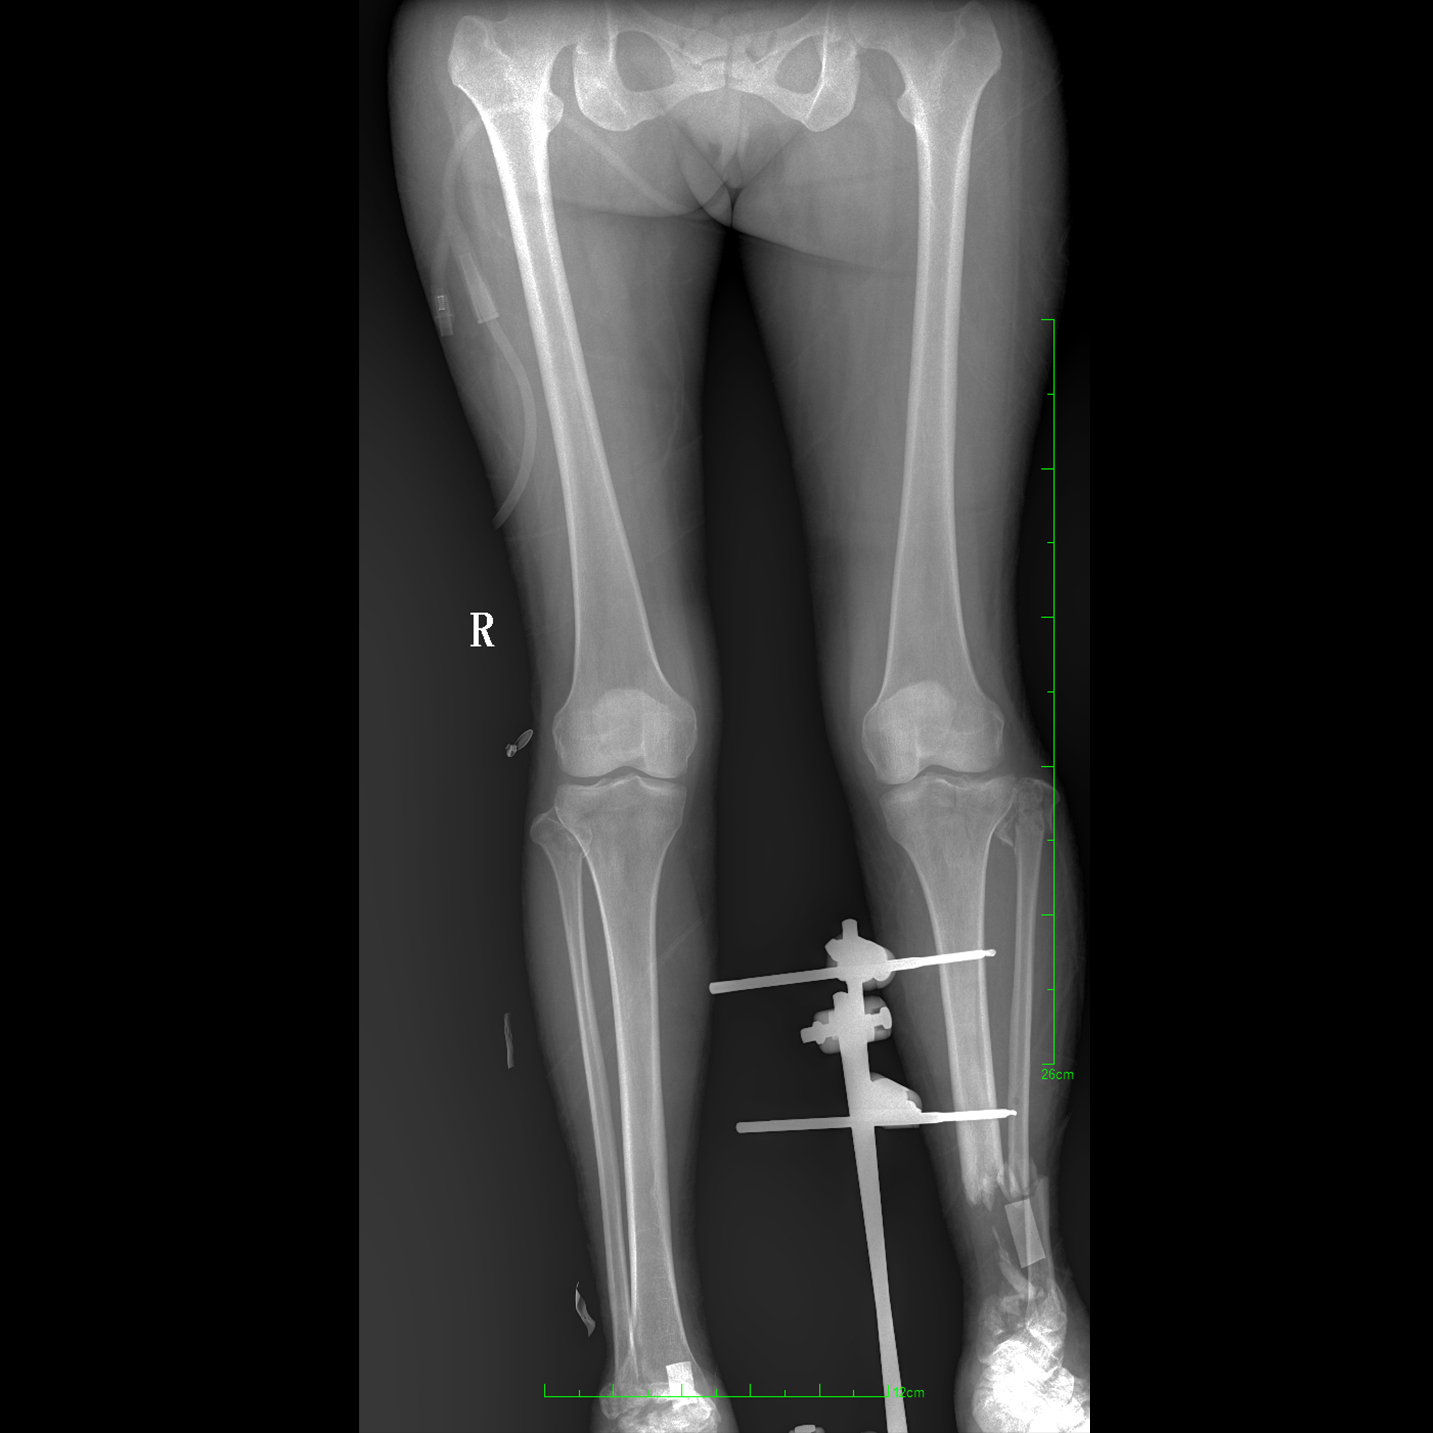

17"*34"有效視野,一次成像不拼接。相較于多張攝影再軟件拼接的DR設(shè)備,PLX8600解決了拼接圖像存在密度不均勻,拼接處圖像配準(zhǔn)和放大效應(yīng)等問題,給臨床帶來了大視野影像解決方案,可一次性覆蓋全脊柱或雙下肢影像。

除常規(guī)靜態(tài)攝影外,PLX8600大平板具備動(dòng)態(tài)透視和點(diǎn)片功能,透視采集功能可支持大視野、多角度的可視化觀察。通過可視化的動(dòng)態(tài)影像,配合點(diǎn)片功能,能夠很好的觀察復(fù)雜部位病灶,有效的抓取關(guān)鍵幀,降低患者多次攝片的概率。如:全脊柱狀態(tài)評(píng)估、長(zhǎng)骨關(guān)節(jié)活動(dòng)度、下肢靜脈造影瓣膜功能評(píng)估、消化道功能評(píng)估、脊髓造影等更多大視野臨床應(yīng)用。